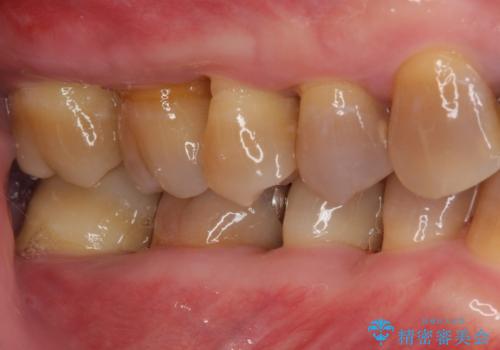

- 幼少期の薬剤の影響で歯が変色していていることを気にして来院された患者様です。

仕事も落ち着き、長年気にしていた前歯の色をきれいにしたいとのことでした。

上下ともに前歯のセラミッククラウンによる補綴治療を希望されていましたが、下顎前歯は叢生が強いため、補綴治療前に部分矯正を行って歯列を整えた上で、補綴治療を行うこととしました。